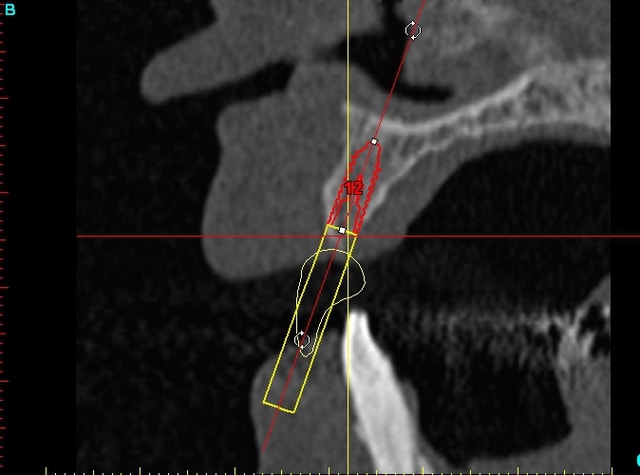

14dar tm9a6n - Eugenol

15dar srylok - Eugenol

12